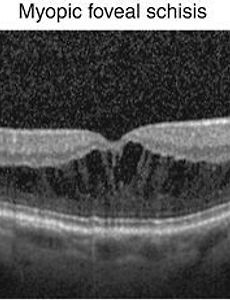

병적 고도근시와 후포도종(posterior staphyloma), 중심와 분리증(myopic foveoschisis), 근시성 황반원공(myopic macular hole) 눈의 도수로는 -6 디옵터의 굴절력, 안구의 길이로는 26 mm 의 안축장을 넘는 심한 고도근시에서, 시력 장애를 유발할수 있는 이차적인 안저 변화가 동반된 경우를 병적인 고도근시 (pathologic high myopia)라고 합니다. 이러한 병적 고도근시는, 성장과정에서 발생한 일반적인 고도근시와는 달리, 눈의 도수는 점점 나빠지고, 안축장의 길이 역시 점점 나빠지는것이 특징입니다. 이러한 병적 고도근시에서 가장 중요한 소견은, 안구에서 가장 질긴 조직이자, 안구의 형태를 유지해주는 가장 중요한 조직인 공막(sclera)조직이 늘어나고, 약해지는 것입니다. 이를 안구조직이 포도송이 처럼 늘어난다고 하여, 안구 포도종 (staphyloma)이라고 하며, 특히 안구의 뒤편이 늘어나기 때문에, 이를 안구 .. 2018. 6. 24.